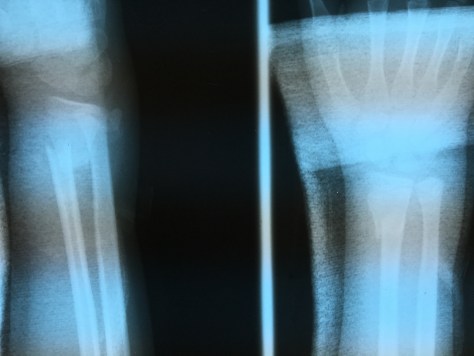

This young man fell and broke his wrist. He and his dad finally made it to our hospital 7 days later. They had gone to a hospital near their home that had the technology to do an X-ray, but not the wisdom or training to do anything other than put him in an ace wrap. So his wrist flopped around broken and displaced for a week. His dad said that he was told to go to the city in La Ceiba to have surgery on it, but then the Lord put it in his heart to bring him out to our hospital in the jungle to have it cared for. And we did!